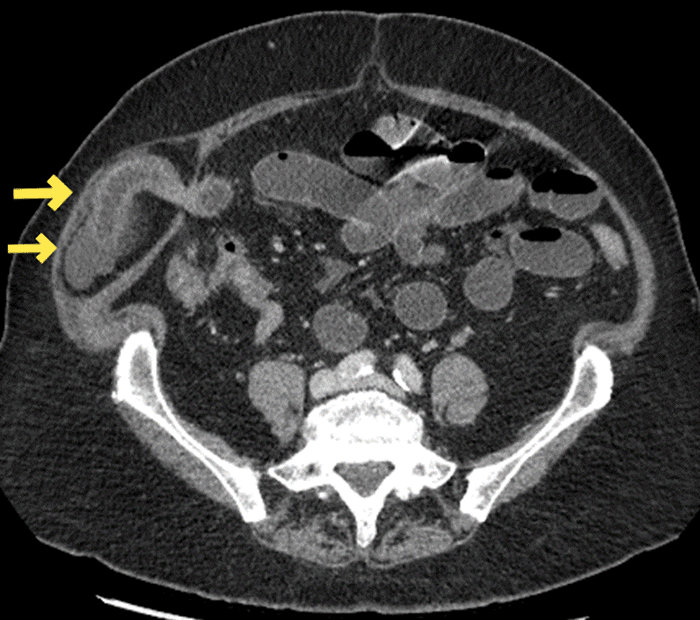

The patient is a 78-year-old female with a history of open appendectomy, open cholecystectomy, and open hysterectomy presented with typical bowel obstruction symptoms, including abdominal pain, distension, nausea, and vomiting. She was hemodynamically stable and with normal labs but exquisitely tender over an indiscrete bulge in her right lower quadrant, which was not reducible. A CT abdomen and pelvis demonstrated bowel obstruction as a result of a Spigelian hernia, as shown in Figure 1 and Figure 2.

Figure 1. Axial View of Spigelian-type Incisional Hernia. Published with Permission

Note compression of the herniated ileum and free fluid within the hernia sac